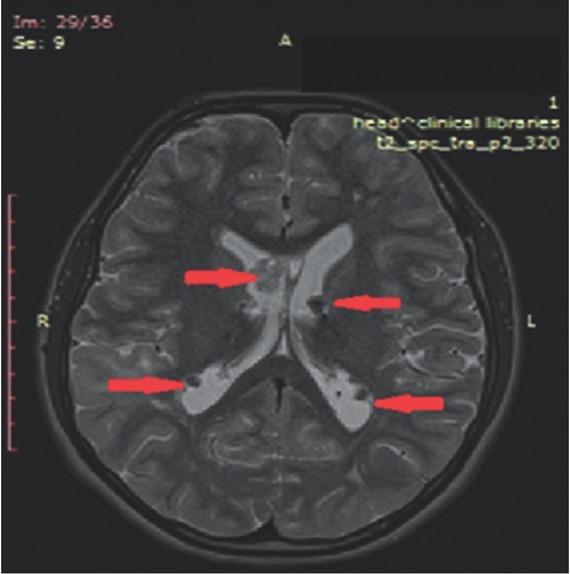

Figure 2

On the brain MRI, multiple lesions as subependimal nodules, subcortical tubers and largest tumor mass presented in foramen Monro as SEGA (diameter 3.0 × 1.5 cm) were described.

Due to the presence of a large brain structural manifestation, continuous follow-up by a neurologist and a neurosurgeon was performed. The majority of TSC patients have neurological symptoms, ~90.0% of affected individuals experience seizures and almost half also experience cognitive impairments, autism, or other behavioral disorders. Epilepsy is seen in 70.0-90.0% of patients, most commonly presenting in the first year of life [12]. Our patient had normal mental status without autism and/or behavioral difficulties. However, seizures were present from the first year of life, with prescribed therapy till 5 years. At the age of 12 years, when the new onset of seizures was registered, an anticonvulsive treatment was reinitiated. After many years free of seizures, the anticonvulsive therapy was again ceased. Thus, after 3 years undergoing everolimus therapy, a new episode of seizure was reported and anticonvulsive therapy was administered. The patient was placed on lamotrigin. The MRI findings excluded hydrocephalus without necessity of surgical treatment. Based on the literature, surgical intervention of SEGA >3 cm has 67.0% risk of surgery-related complications and surgery on tumors >4 cm was associated with 73.0% risk of complications [21,22].